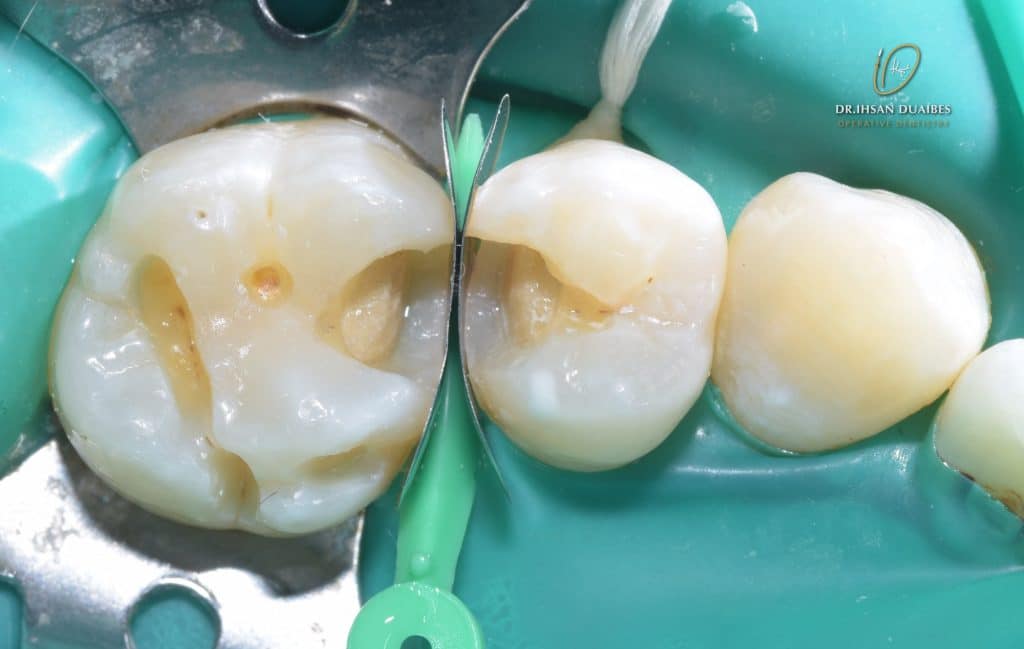

Building proximal walls ,then Remove the matrix ( Remove matrix stripes with mosquitto )

Dentine layer A3.5

Premolar restored

Molar restored